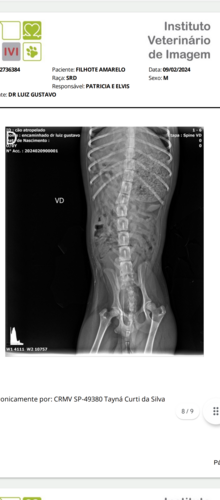

Me chamo Nayara e vou contar um pouco de um acidente que houve comigo e meu marido, eu e meu marido estávamos indo para o trabalho quando um cachorrinho entrou na frente do nosso carro e infelizmente não deu tempo de nada e acabamos batendo nele. Preciso muito da ajuda de vocês para os custos porque não estamos com condições no momento de ajudar em tudo que ele precisa qualquer ajuda será muito bem vinda, hoje pela manhã recebemos o laudo do raio-x, ele está com uma fratura na coluna vertebral e possivelmente precisará de cirurgia já entrei em contato com algumas clínicas de Ponta grossa que é a cidade mais perto que realiza esse procedimento porém não é certeza que o caso dele se resolva com a cirurgia caso não tenha solução ele ficará de cadeira de rodas. Estamos torcendo que a cirurgia de certo que apesar só custo será o melhor para ele.